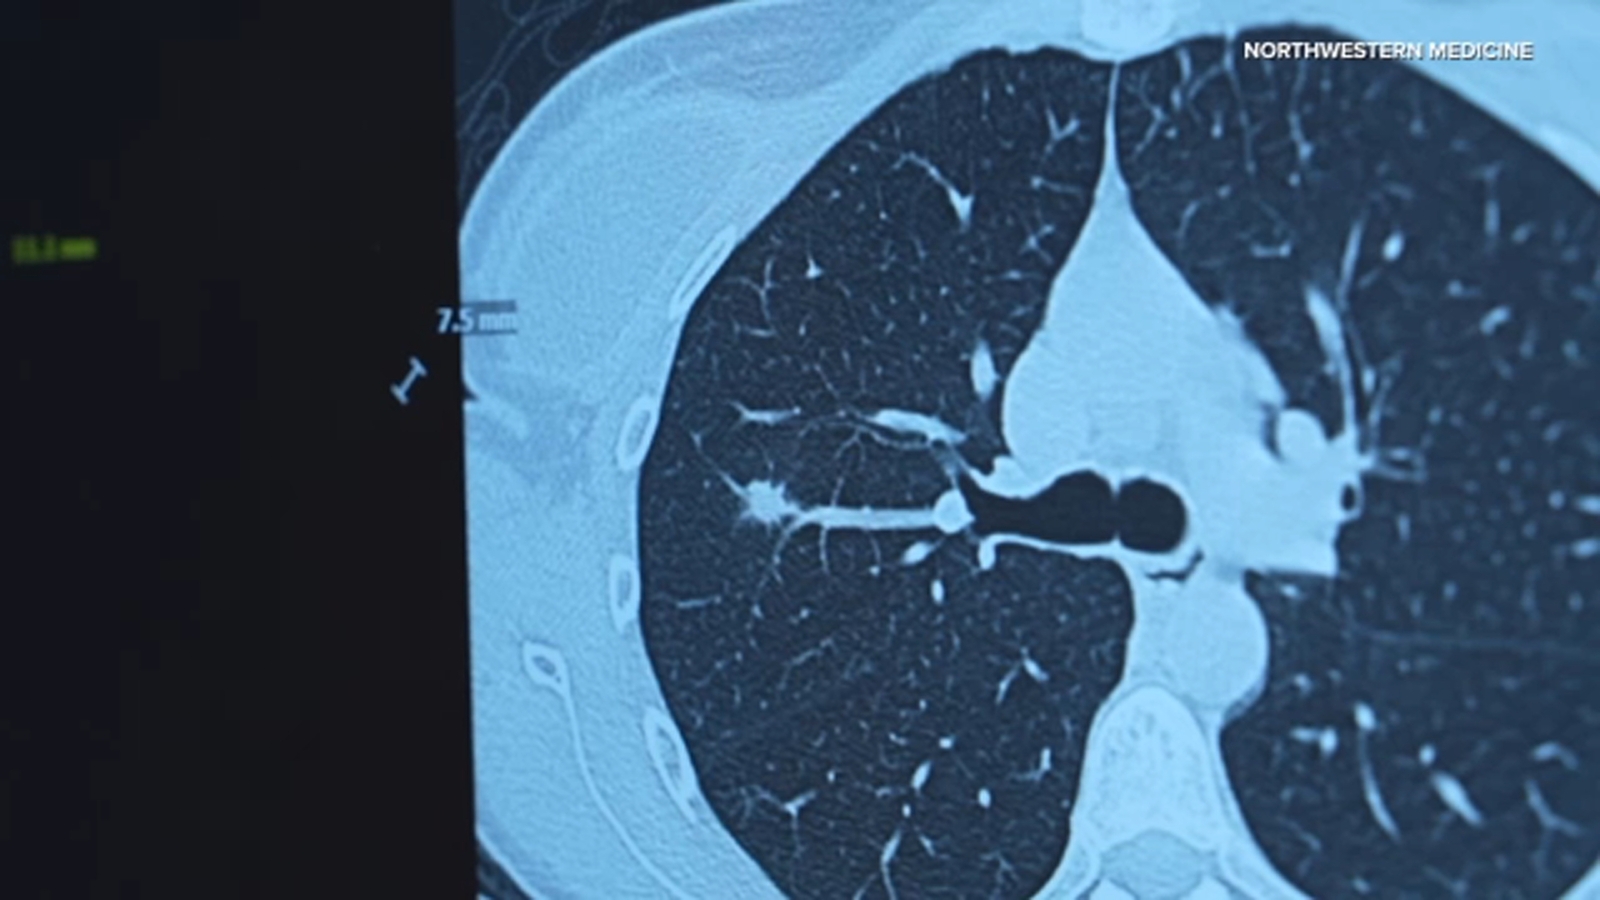

Hal ini mendorong Northwestern Medicine untuk memperluas program skrining CT dosis rendah. Mereka akan menyediakan fasilitas yang lebih komprehensif untuk mendeteksi kondisi paru-paru, jantung, dan tulang sejak dini. Langkah ini diharapkan dapat menjangkau lebih banyak individu yang berisiko.

Skrining dini di Northwestern Medicine menggunakan pemindaian yang memakan waktu kurang dari 10 detik. Proses ini tidak memerlukan pewarna tambahan tetapi memberikan gambaran lengkap tentang rongga dada. Hasil pemindaian tersebut menghasilkan gambar dasar yang dapat disimpan pasien sepanjang hidup.